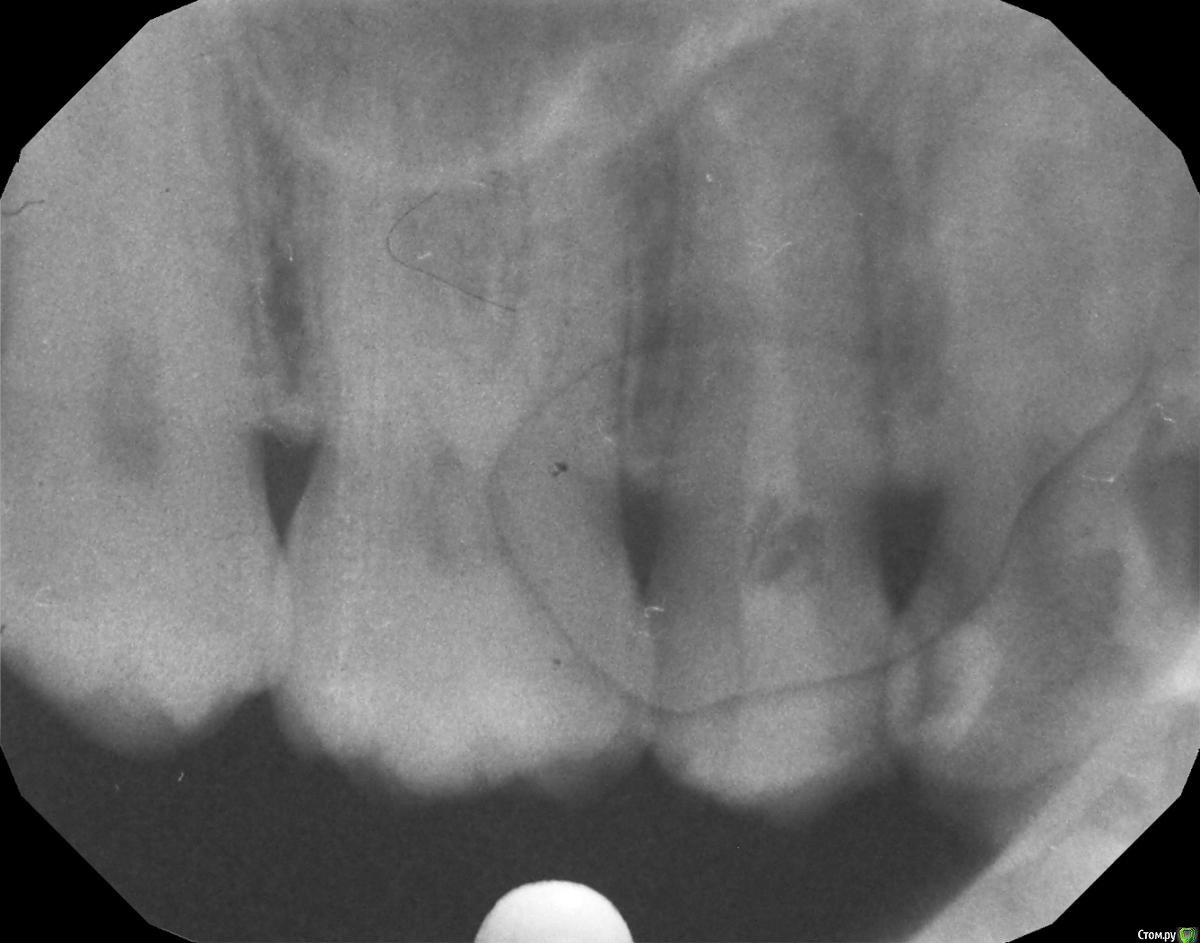

Валентина85 Опубликовано 6 августа, 2016 Поделиться Опубликовано 6 августа, 2016 Доброго дня! Зуб 1.4 после пломбирования глубокого кариеса реагирует болью, если на него попадает что-то мелкое и жесткое (семечко, крошка от сухаря и т.п.), реагирует всегда примерно в одной точке. Предлагают заменить пломбу. Но есть один интересный момент - при замене пломбы высокий риск сотворить ятрогенное вскрытие пульпы - там остался очень тонкий слой дентина. Что будет меньшее из зол - жить с дебондингом или любой ценой избавляться от него рискуя заиметь пульпит? Ссылка на комментарий

Валентина85 Опубликовано 7 августа, 2016 Автор Поделиться Опубликовано 7 августа, 2016 А чувствительная точка на поверхности пломбы или зуба?пломбы пломба не завышает - проверяли копиркойпульпита/периодонтита нет - проверяли холодомтест на трещину с накусыванием валика отрицательныйпрощупывали зондом границу пломба-зуб - краевое прилегание норм Ссылка на комментарий